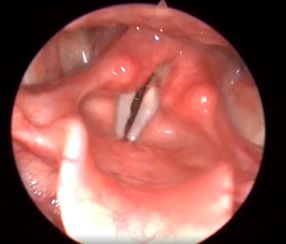

Клинический пример №2. Хирургическое лечение двустороннего паралича гортани с использованием лазера 445 нм.

Лечение данных пациентов в нашей клинике проводится по разработанному методу Кривопаловым А.А., д.м.н. зав. НИО патологии верхних дыхательных путей. Данная методика себя очень хорошо зарекомендовала.

После операции воспалительные проявления со стороны голосовой складки слабо выражены. Через месяц после операции пациенты готовы к следующему этапы реабилитации – занятие с фонопедом.

Рис 2А. Двусторонний паралич гортани. До операции.

Рис 2Б Двусторонний паралич гортани. 7 сутки после операции